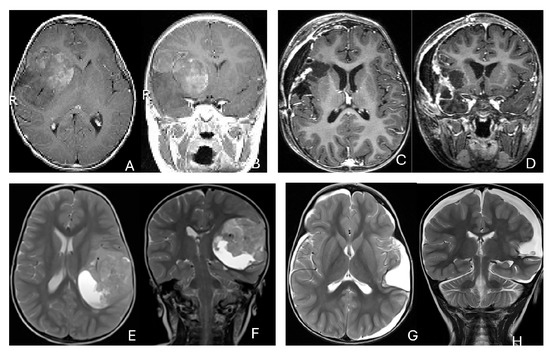

The integration of molecular features into histopathological diagnoses has become central to the World Health Organization (WHO) classification of central nervous system (CNS) tumors, improving prognostic accuracy and supporting precision medicine. However, unequal access to molecular testing limits the universal application of integrated diagnosis. To address this, artificial intelligence (AI) models are being developed to predict molecular alterations directly from histological data. In gliomas, deep learning applied to whole-slide images (WSIs) of permanent sections achieves neuropathologist-level accuracy in predicting biomarkers such as IDH mutation and 1p/19q co-deletion, as well as in molecular subtype classification and outcome prediction. Recent advances extend these approaches to intraoperative cryosections, enabling real-time glioma grading, molecular prediction, and label-free tissue analysis using modalities such as stimulated Raman histology and domain-adaptive image translation. Beyond gliomas, AI-powered histology is being explored in other brain tumors, including morphology-based molecular classification of spinal cord ependymomas and intraoperative discrimination of gliomas from primary CNS lymphomas. This review summarizes current progress in AI-assisted molecular profiling prediction of brain tumors from tissue, highlighting opportunities for rapid, accurate, and globally accessible diagnostics. The integration of histology and computational methods holds promise for the development of smart AI-assisted neuro-oncology.